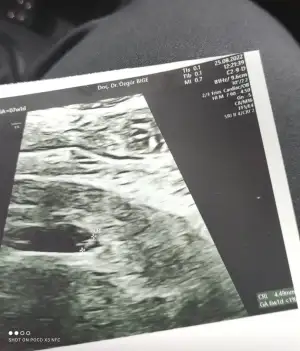

Bebeğin 0.64 cmEki Görüntüle 3118881

Anladım çok teşekkür ederimBebeğin 0.64 cm

6+3 gün ile uyumlu canım

0.27 cm 5+6 ile uyumlu mu peki canım yoksa çok küçük müBebeğin 0.64 cm